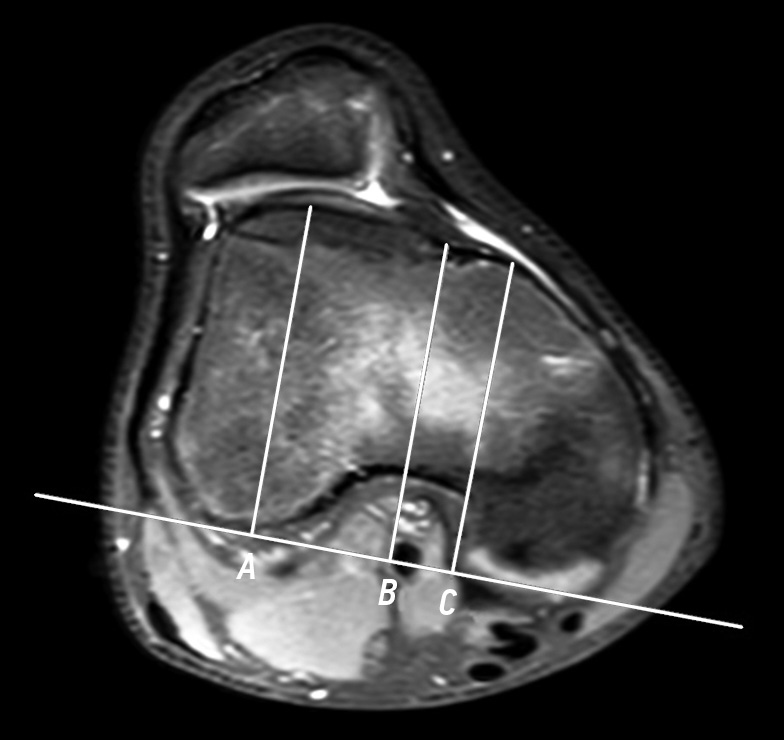

Furthermore, the depth of the trochlear groove was assessed using axial slices. The measurement was performed using the formula ([A + B/2] − C) proposed by Pfirrmann et al. [14]. Distances A and B were defined as the maximal anteroposterior measurements from the posterior aspects of the femoral condyles to the subchondral bone of the trochlear groove at the lateral and medial sides, respectively. Distance C represented the minimal anteroposterior distance from the deepest point of the trochlear groove to a line parallel to the posterior contours of the femoral condyles (Fig. 3).

Fig. 3. Trochlear groove depth measurement on magnetic resonance imaging in a 16-year-old female with patellar instability: A, maximal anteroposterior distance between the femoral condyles and lateral facet; B, maximal anteroposterior distance between the femoral condyles and deepest point of the trochlear groove; and C, maximal anteroposterior distance between the femoral condyles and medial facet.